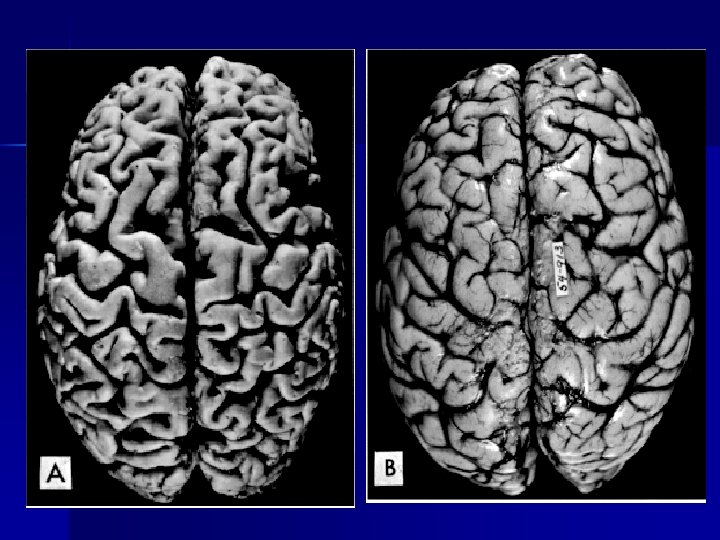

- Atrofia senil. Disminución del tamaño de los órganos, envejecimiento “fisiológico” - Atrofia de la médula ósea: anemia aplásica. - Atrofia generalizada- caquexia – cáncer – hipopituitarismo (envejecimiento precoz).

Mecanismos n n n Disminución de la síntesis Mecanismos endocíticos: vacuolas autofágicas. Gránulos de lipofuscina que cuando alcanzan una cantidad suficiente hace que el órgano adquiera un color marrón. (atrofia parda, corazón y cerebro) Vía proteasomas: proteólisis acelerada

Atrophy of the brain